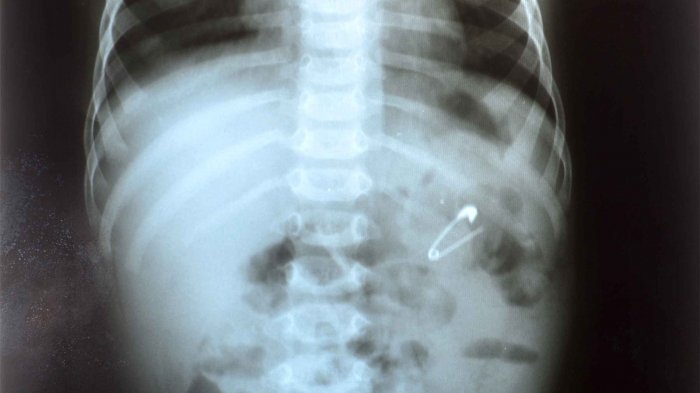

Mengerikan! Ini 10 Benda Aneh yang Ditemukan Di Perut Manusia, Ada Paku Hingga Ponsel

Tidak hanya makanan ada berbagai macam barang seperti baterai ponsel, paku hingga gunting pernah ditemukan dalam perut manusia.